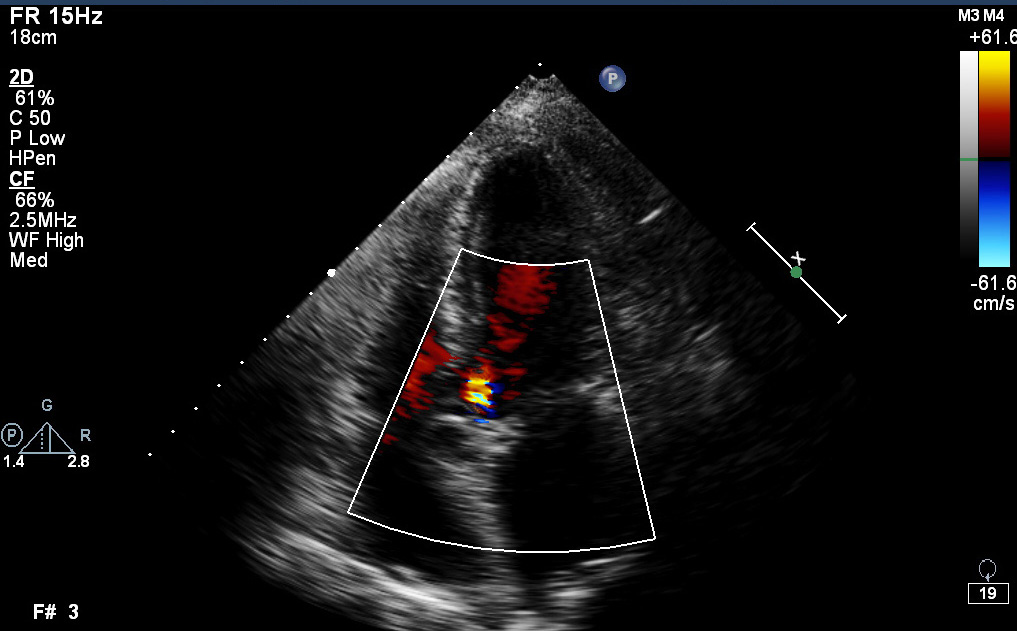

Preoperative echocardiography demonstrated a dilated sinutubular junction (STJ), preserved sinus dimensions and moderate to severe aortic valve insufficiency with central regurgitant jet.

During surgery, comprehensive visual assessment of aortic cusp configuration revealed prolapse of the non-coronary cusp, which was repaired by appropriate techniques. Ascending aorta pathology was corrected with sinutubular junction remodelling (STJR).